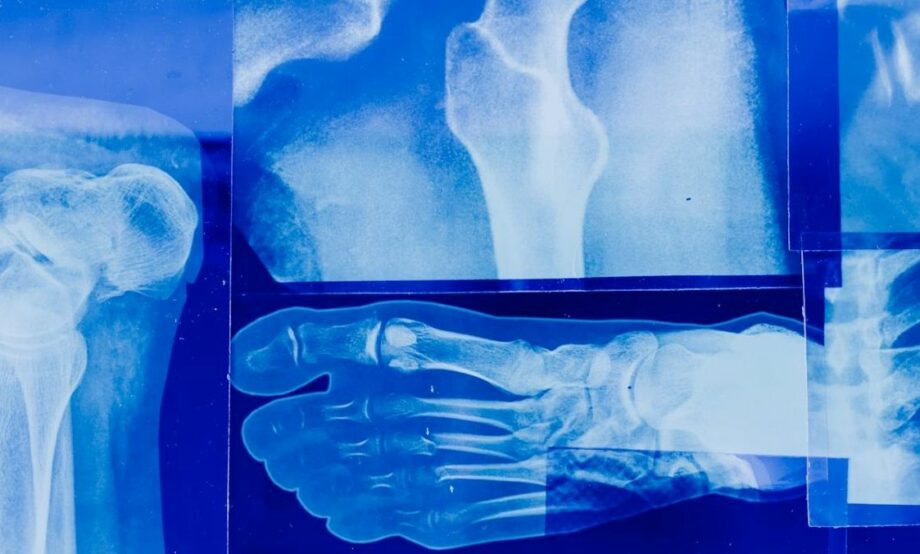

El doctor Miguel Bernal Lemus, del Servicio de Ortopedia del Hospital General de México, en entrevista con Once Noticias Meridiano, explicó que la osteoporosis es una enfermedad caracterizada por la pérdida de la masa ósea, una disminución en la densidad del hueso, la cual traer consecuencias como huesos frágiles y fracturas.

“Le dicen la enfermedad silenciosa porque no da un síntoma característico, algunas personas dicen que presentan dolor, pero realmente es atribuido al desgaste articular, la osteoporosis no da un síntoma, simplemente cuando hay una caída o un golpe leves se presentan las fracturas, el problema es que se da principalmente en cadera, columna y en las muñecas, y esto causa deterioro funcional”, señaló.

El médico agregó que el estudio que se usa para diagnosticar la osteoporosis es la densitometría ósea y se recomienda hacerlo después de los 50 o 60 años de edad y de forma periódica.